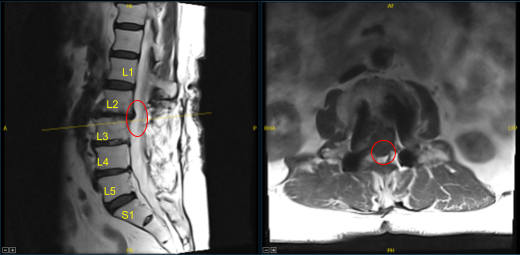

This patient had previously undergone an instrumented arthrodesis at an outside facility at L3-5. They presented with right anterior thigh and left posterior leg pain. Imaging displayed adjacent segment degeneration above and below her fusion mass which correlated well with her symptoms.